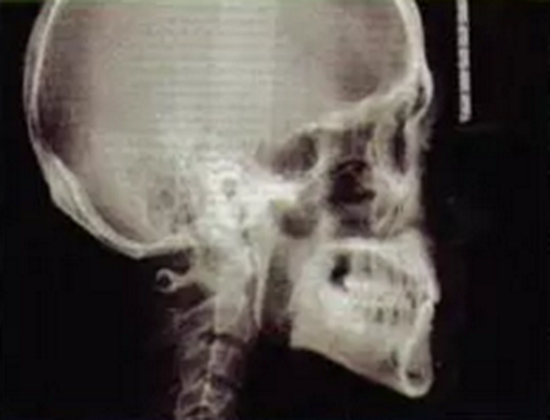

曲面全景片可見1為樁核冠、根尖1/3欠充,但未見陰影。1根方見多生牙高密度影。6遠(yuǎn)中根外吸收、根管欠充,根尖周圍可見透射陰影,牙周膜增寬。上前牙及63近遠(yuǎn)中牙槽骨度輕度水平吸收。1牙根尖片見其牙周膜清晰度尚可,未見根骨粘連。頭顱側(cè)位片測量結(jié)果示患者為I類、均角骨面型,上前牙和下前牙唇傾度減?。▓D3)。

圖4術(shù)前頭顱側(cè)位片